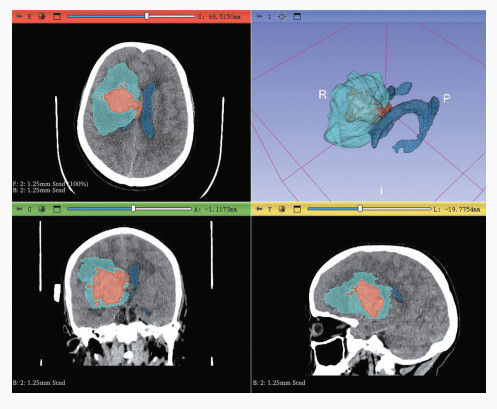

Cao L , Liu M , Wang M , Ding J , Mao K , Liu K , Li S . 3D Slicer-based calculation of hematoma irregularity index for predicting hematoma expansion in intracerebral hemorrhage. BMC Neurol, 2022, 22: 452.

doi: 10.1186/s12883-022-02983-w